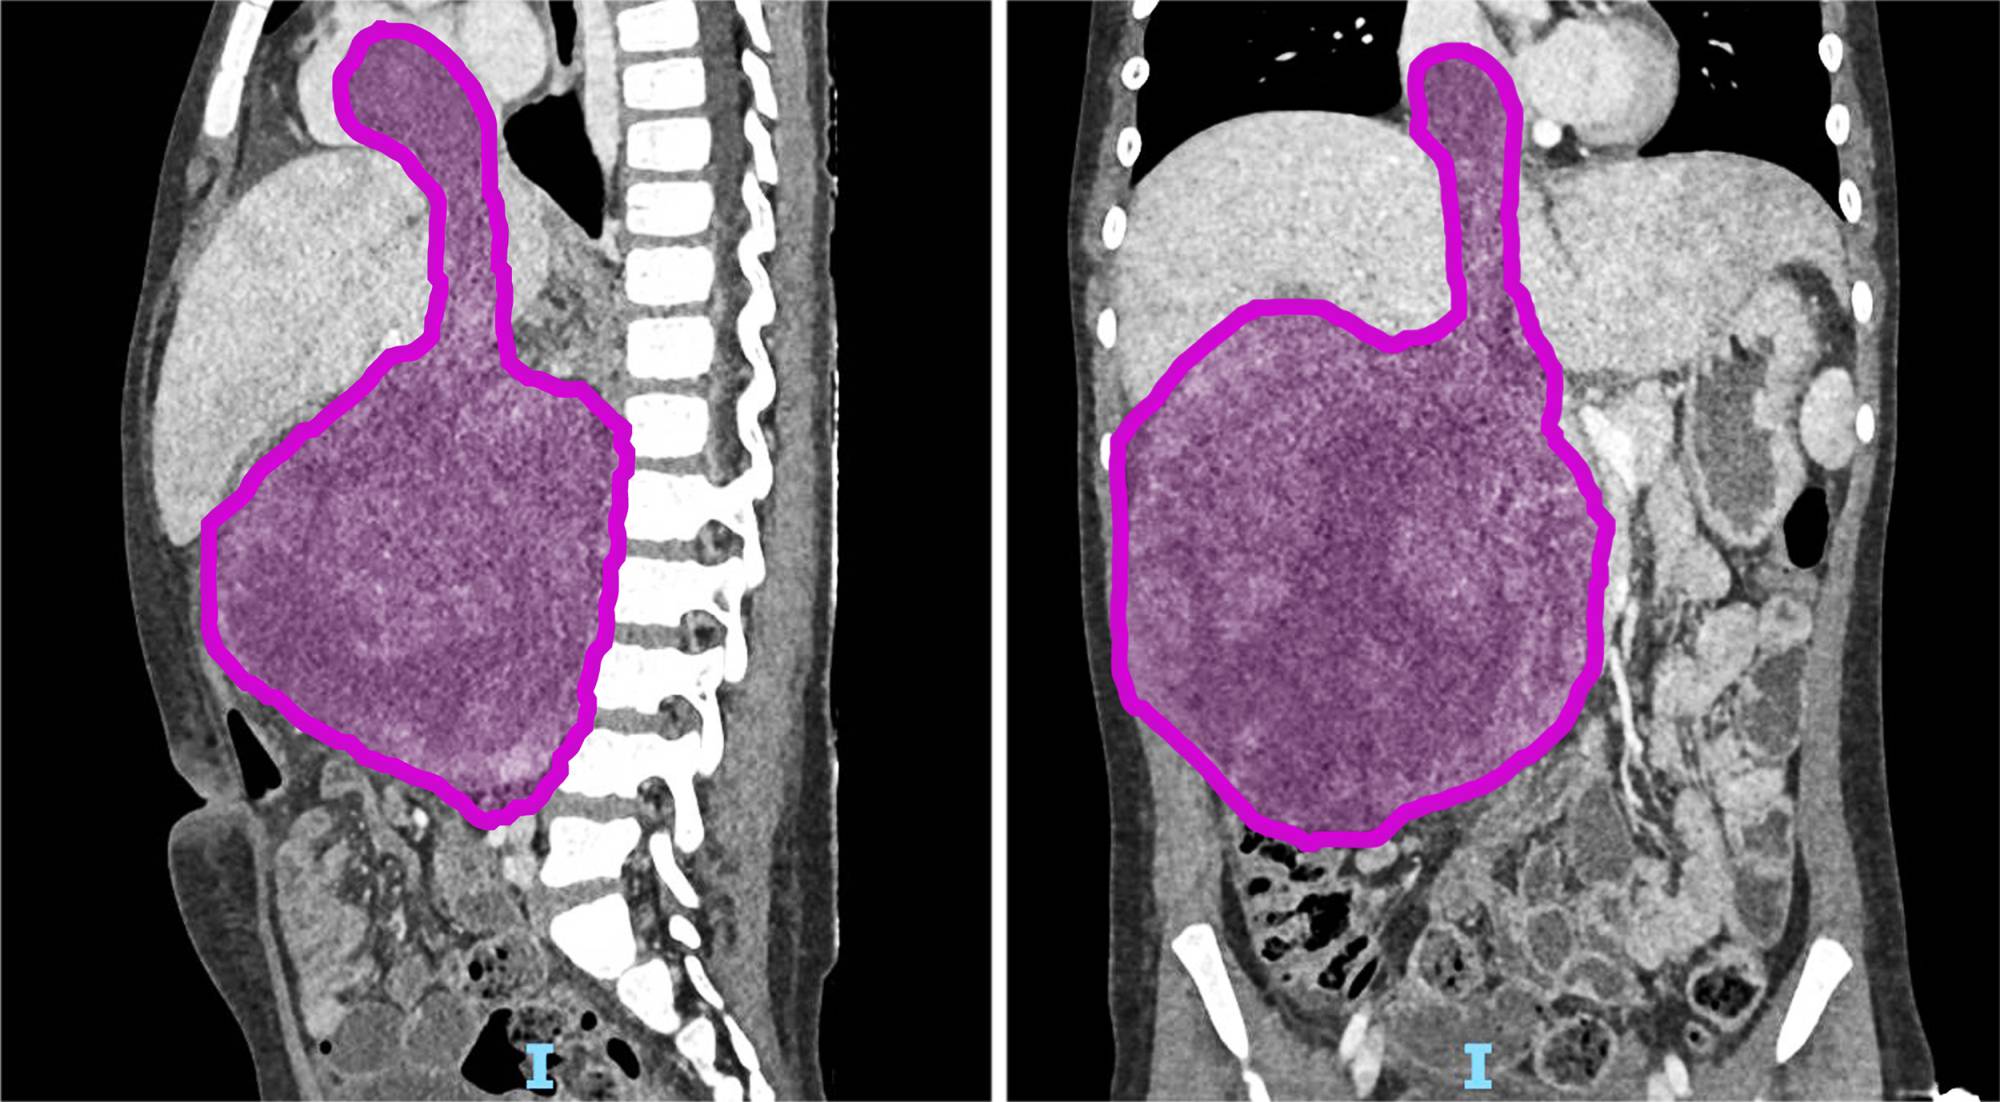

Sara (ma il nome di fantasia), otto anni appena compiuti, era affetta da un nefroblastoma al rene destro che si estendeva all’interno della vena renale, della vena cava inferiore fino a raggiungere l’atrio destro del cuore, a causa di una trombosi neoplastica. Questa rara estensione del tumore si verifica in appena il 4-10% dei casi di nefroblastoma. Prima dell’intervento Sara è stata sottoposta a sei cicli di chemioterapia, eseguiti dal team di oncologi guidati dal professor Franco Locatelli, per ridurre la massa tumorale e facilitare l’operazione. La fase preparatoria pre-chirurgica si è avvalsa di tecniche all’avanguardia di diagnostica per immagini come l’elaborazione 3D del tumore da asportare realizzata dall’unità di Imaging avanzato cardiotoracovascolare e fetale.

L’operazione ha avuto una prima fase in cui l’équipe di chirurgia oncologica, formata dal dottor Alessandro Crocoli e dalla dottoressa Chiara Grimaldi, ha rimosso il rene destro, il cui volume era dieci volte superiore rispetto alla norma a causa del tumore. Successivamente i cardiochirurghi, guidati dal professor Lorenzo Galletti e con il dottor Gianluca Brancaccio come primo operatore, hanno temporaneamente arrestato il cuore della bambina, mantenendola in vita con la circolazione extracorporea, per rimuovere la parte del tumore che aveva invaso l’atrio destro. Infine, dopo aver riavviato il cuore, i chirurghi hanno completato l’operazione rimuovendo il residuo tumorale dalla vena cava inferiore. In totale, il tumore asportato pesava circa 1,5 kg. La parte anestesiologica del complesso intervento, durato più di 9 ore, è stata gestita dal team della Terapia Intensiva Cardiochirurgica del dottor Luca Di Chiara.